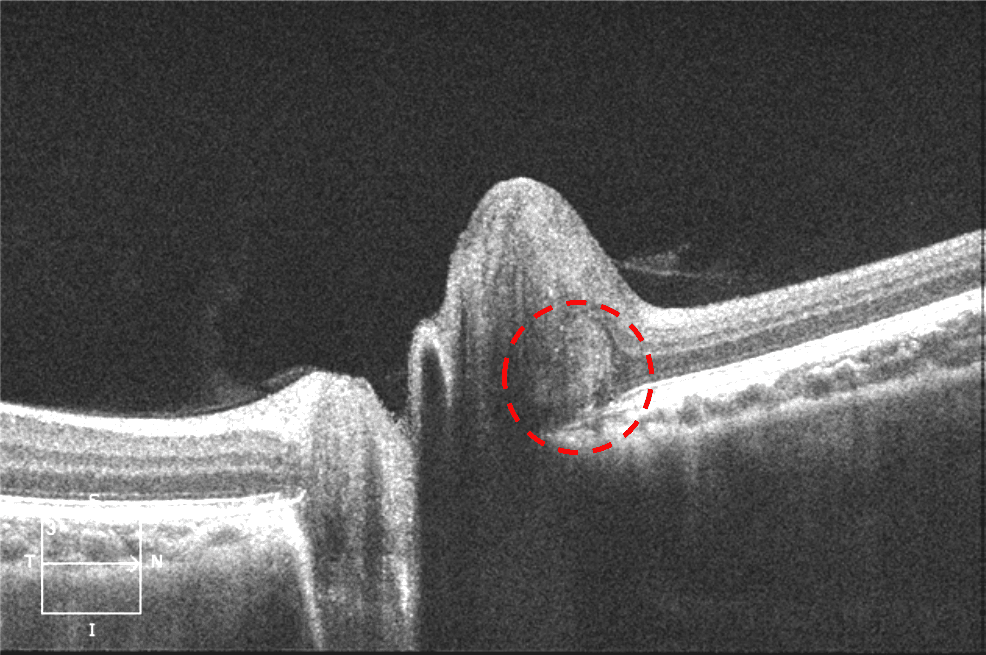

OCT of the Elevated Optic Nerve Head

OCT sections illustrating the "embedded" optic nerve (EON). (AC How To Read Oct Optic Nerve Each oct curates a ring scan involving the optic nerve: This article outlines the basics of oct imaging and walks you through how to analyze retinal nerve fiber layer (rnfl) thickness, macular thickness and ganglion cell. Optical coherence tomography (oct) has revolutionized the diagnostic field of retina in many different ways. Here is a quick primer on how. The peripapillary. How To Read Oct Optic Nerve.